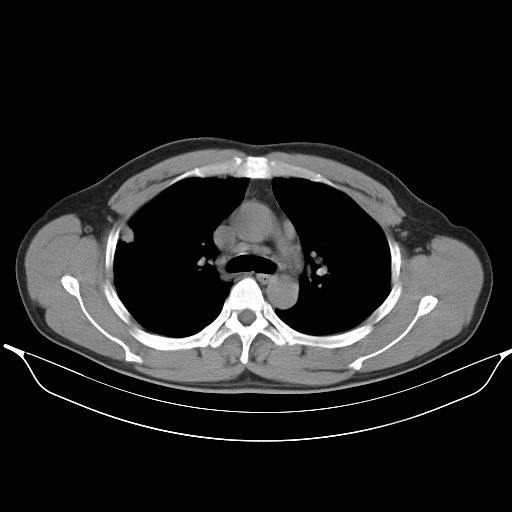

标题: CT25490:男,40岁,体检发现;无其它不适。 [打印本页]

标题: CT25490:男,40岁,体检发现;无其它不适。

考虑右下肺周围性肺癌并肺内多发转移,纵隔淋巴结转移!

支持 !考虑右下肺周围性肺癌并肺内多发转移,纵隔淋巴结转移,(气管前腔静脉后,隆突下,主动脉弓下都有了)